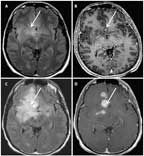

FIGURE 1

MRI of a 41-Year-Old Man With an Anaplastic Astrocytoma, IDH–Wild- Type

A 41-year-old man presented with a generalized seizure. MRI revealed an extensive, diffusely infiltrative, largely nonenhancing lesion within the right frontal and temporal lobes (Figures 1A and 1B). A biopsy of the right frontal lobe demonstrated an anaplastic astrocytoma, IDH1−wild-type. The patient was treated with concurrent radiation and temozolomide followed by adjuvant temozolomide, per standard protocol for glioblastoma. After 1 cycle of temozolomide, his MRI showed progressive disease (Figures 1C and 1D), and rebiopsy demonstrated transformation to glioblastoma.